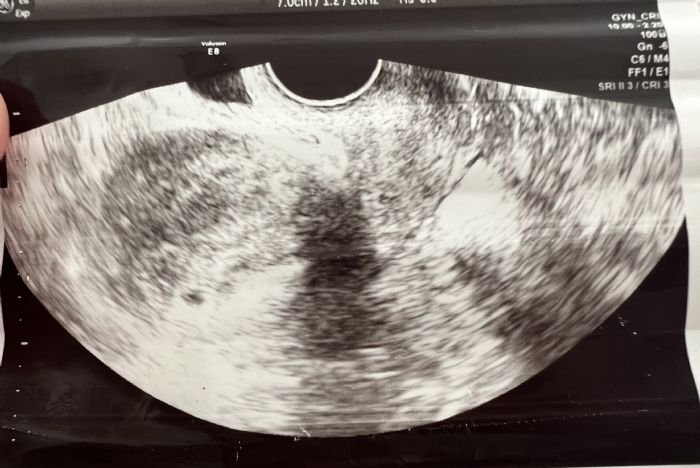

user posted image

Mene pa zanima če katera iz te UZ slike kaj razbere? To je uz za potrditev nosečnost. Samo jaz ne vidim nic 😅 je bilo pa tole komaj 5w5d Če bi vsaj vedela kam gledat za gestacijsko vrečko ali pa je ta slika zelo povečana.🤷‍♀️

uh, iz tega uz-ja pa jaz tudi nič ne razberem. kaj pa je sicer ginekolog rekel? da je zaenkrat vse ok? verjetno je res samo tako zgodaj, da je za nas laike težko kaj prepoznat :D

Iz slikice žal ne znam razbrati ničesar.